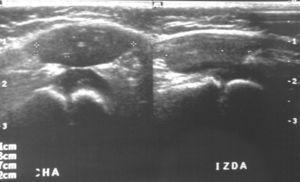

El estudio ecográfico pone de manifiesto una disminución de volumen y alteración de la arquitectura normal de las fibras musculares del vasto intermedio, observándose fundamentalmente en tercio distal un área de mayor ecogenicidad que se interpreta como posible fibrosis (fig. 1).

Figura 1. Ecografía de ambas rodillas en la que se aprecia marcada atrofia del músculo vasto intermedio y un área de mayor ecogenicidad que se interpreta como posible fibrosis.